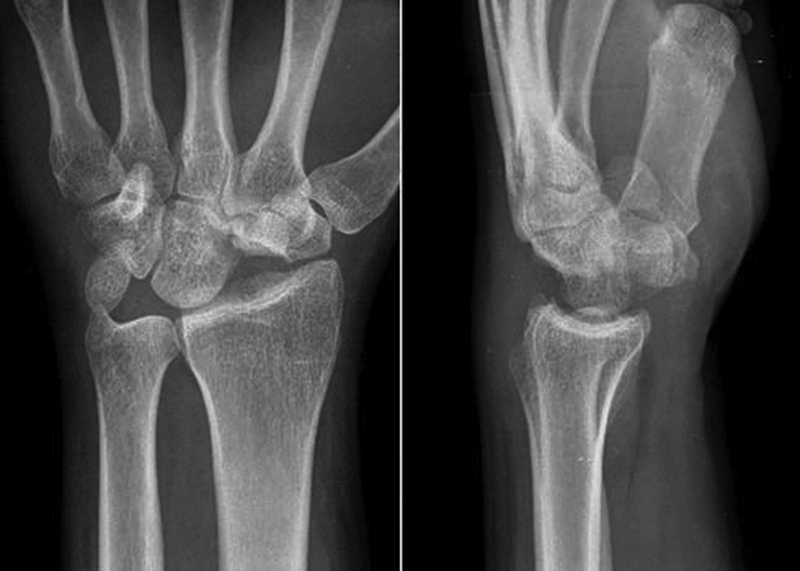

Fig. 4.

Proximal subchondral cleavage planes indicate loss of bone support to the hyaline cartilage surface and preclude use of a core bone flap only for treatment.